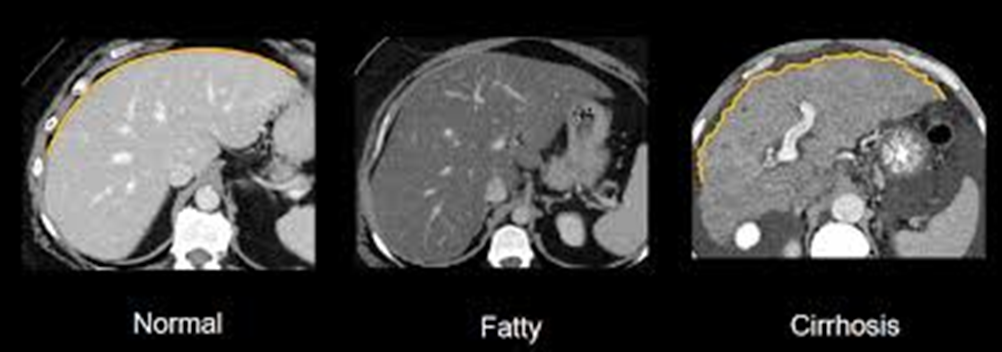

liver imaging uses techniques like ultrasound, CT and MRI to visualise the liver for diagnostic purposes